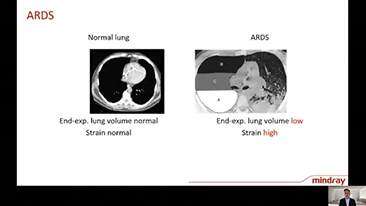

Combinant oxygĂŠnothĂŠrapie Ă haut dĂŠbit (OHD), ventilation non invasive (VNI) et ventilation invasive (VI) les ventilateurs de la sĂŠrie SV 3 en 1 offrent des performances stables, des fonctions polyvalentes et une simplicitĂŠ d'utilisation. Des caractĂŠristiques exceptionnelles de ventilation protectriceet de nombreux outils d'aide Ă la dĂŠcision sont con?us pour rĂŠduire le risque d'infection croisĂŠe et faciliter le travail quotidien du personnel soignant.